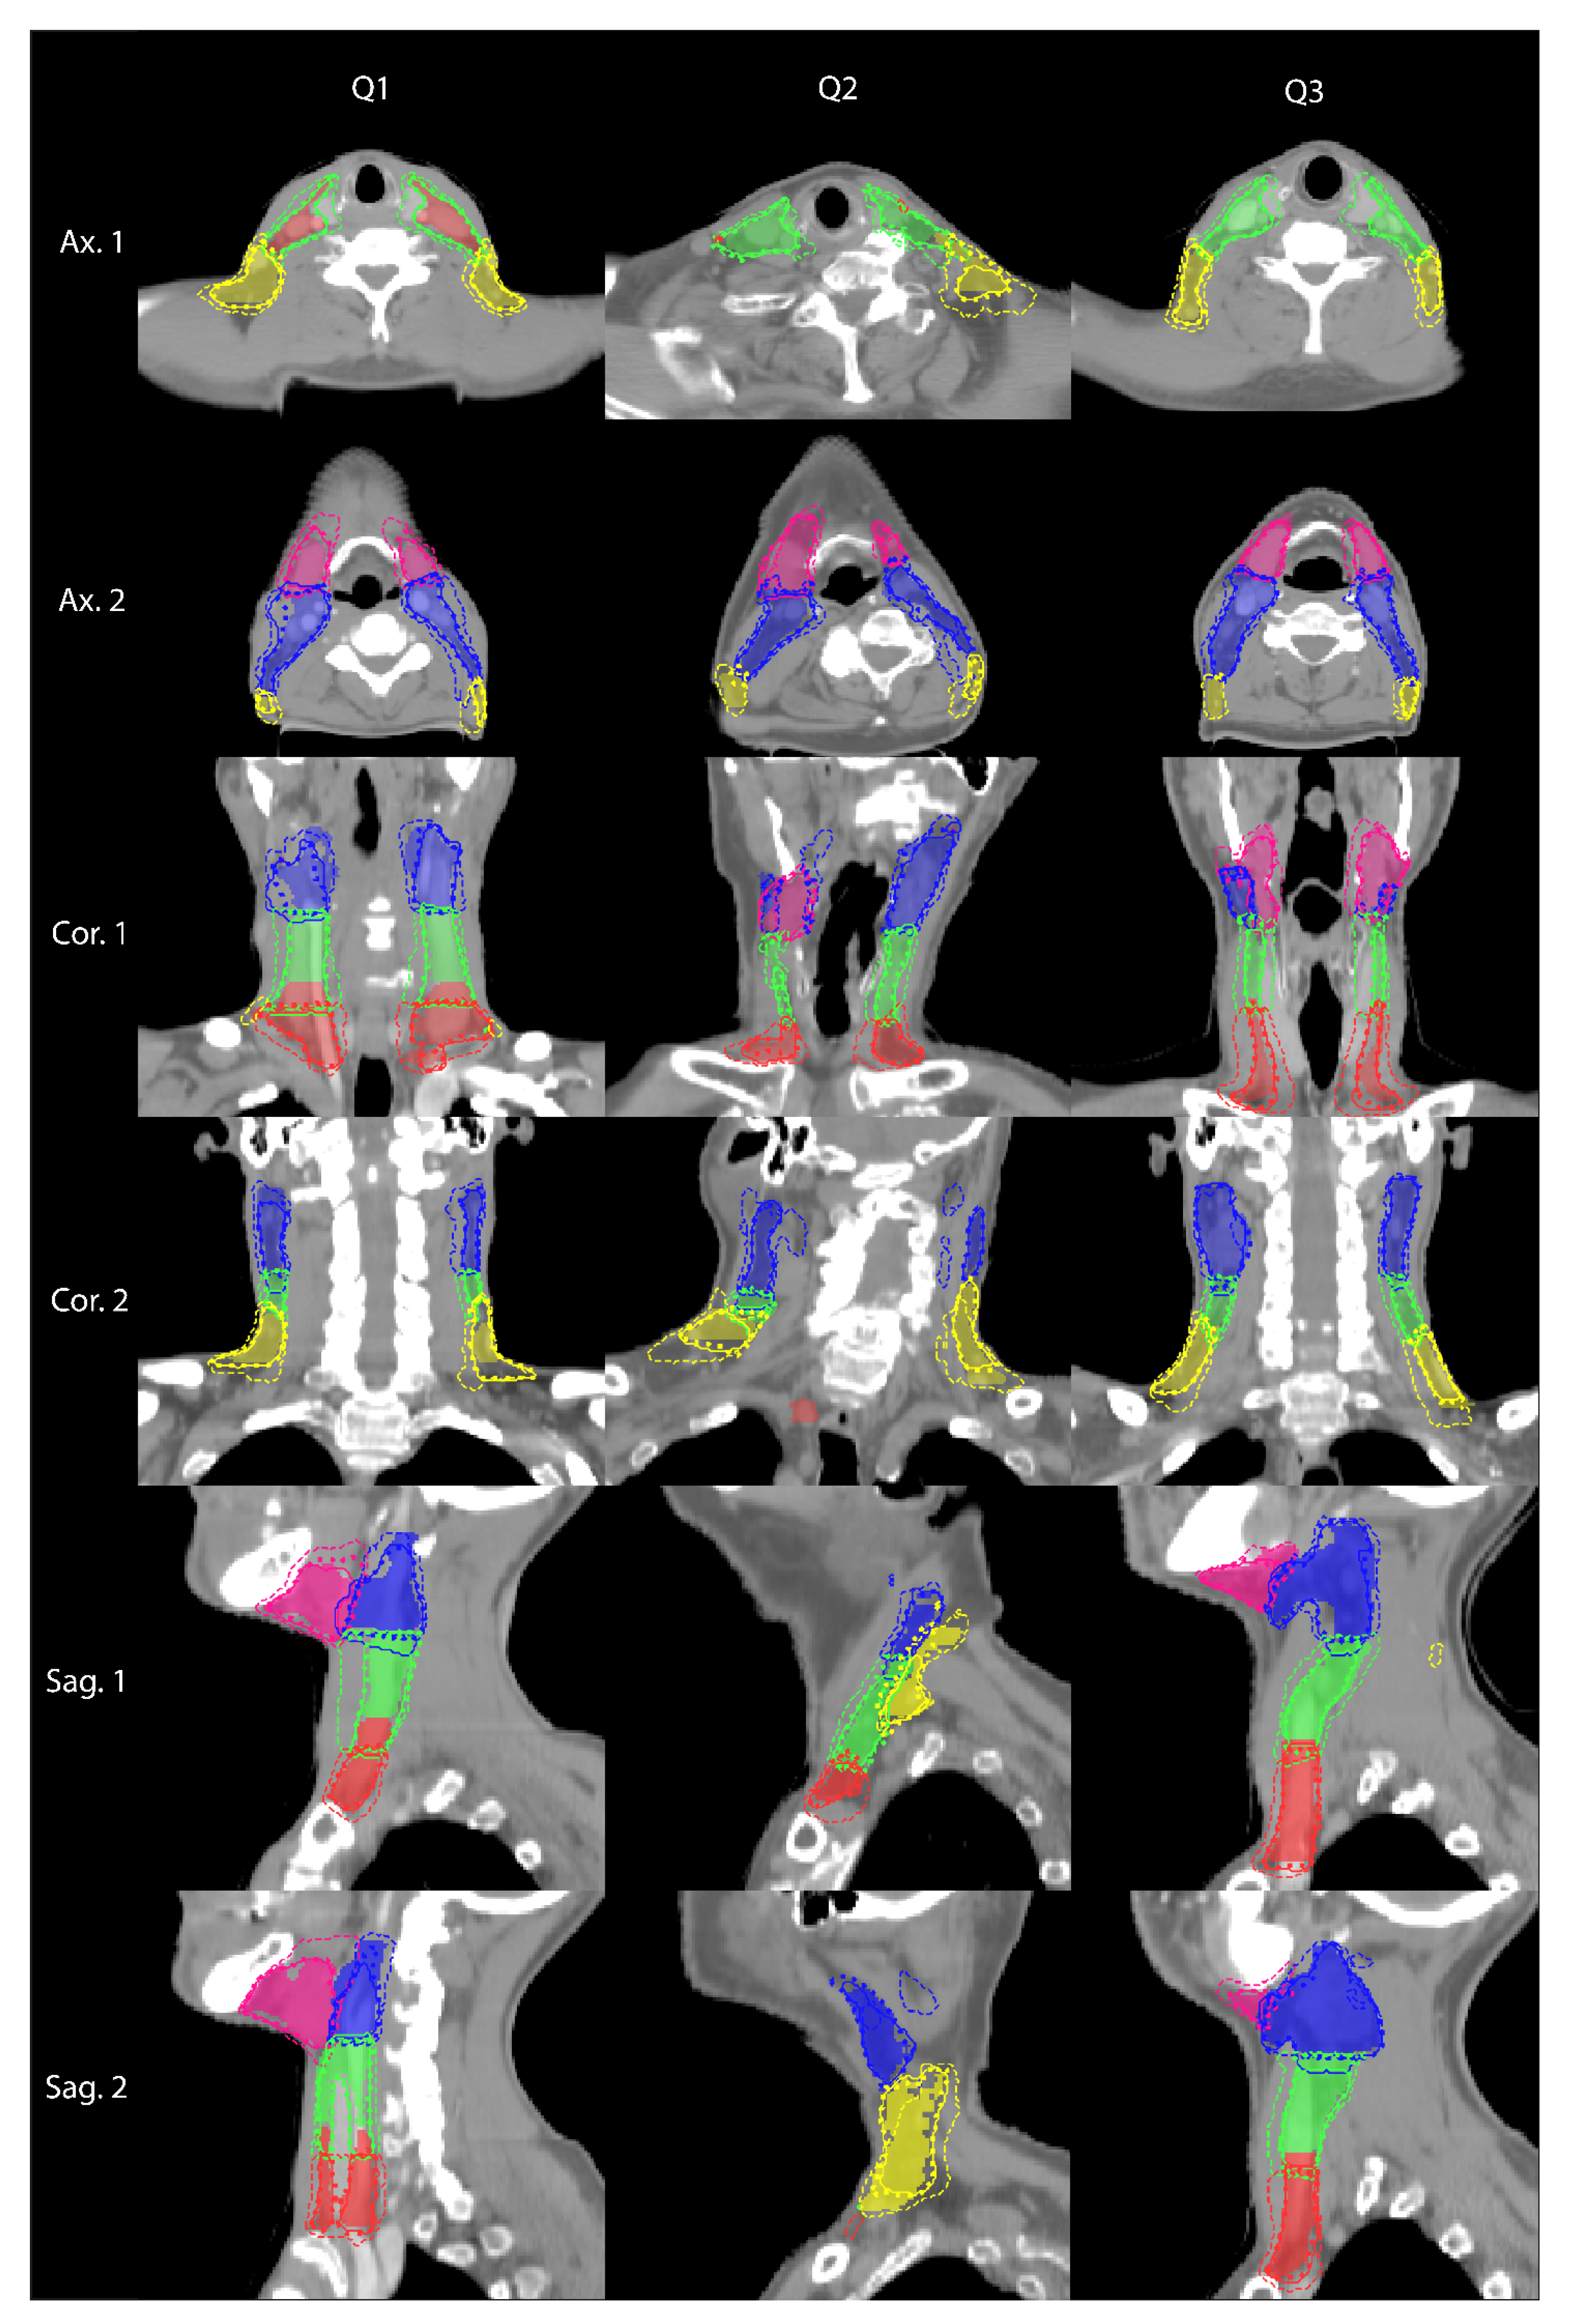

3. Results